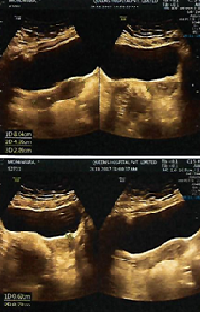

A 60 year old lady from good socio-economic status was evaluated in the Emergency Department of the Addin Sakina Medical College, Jessore with moderately severe lower abdominal pain, marked anorexia, frequent vomiting, high fever with mild abdominal distension, constipation and burning sensation during micturition. The patient was well until 2 weeks before the presentation to the hospital when she develop-ed sudden onset of severe central abdominal pain associated with anorexia and vomiting. Short after, the pain shifted to the right iliac fossa. Later on, the fever developed which was continuous and not associated with chills and rigor. At the same time, she noticed that food aggravated the abdominal pain and discomfort.